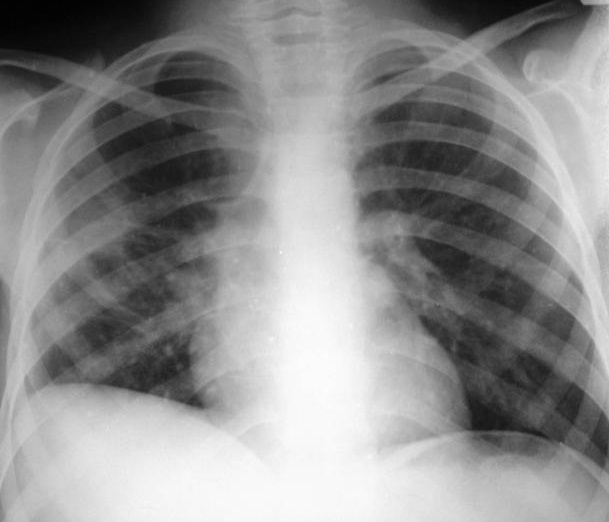

Image radiologique du cliche de face PA d'une

pleuresie de grande abondance avec aspect de opacite

non systematise , n'a pas de bronchogram aerique ,

efface de images vasculaire et de la coupole

diapragmatique à inferieure du poumon droit . La

"courbe parabolique de Damoiseau " est situe en

haute et la shilhouette du coeur et le mediastin est

un legerement decaler vers la gauche . |